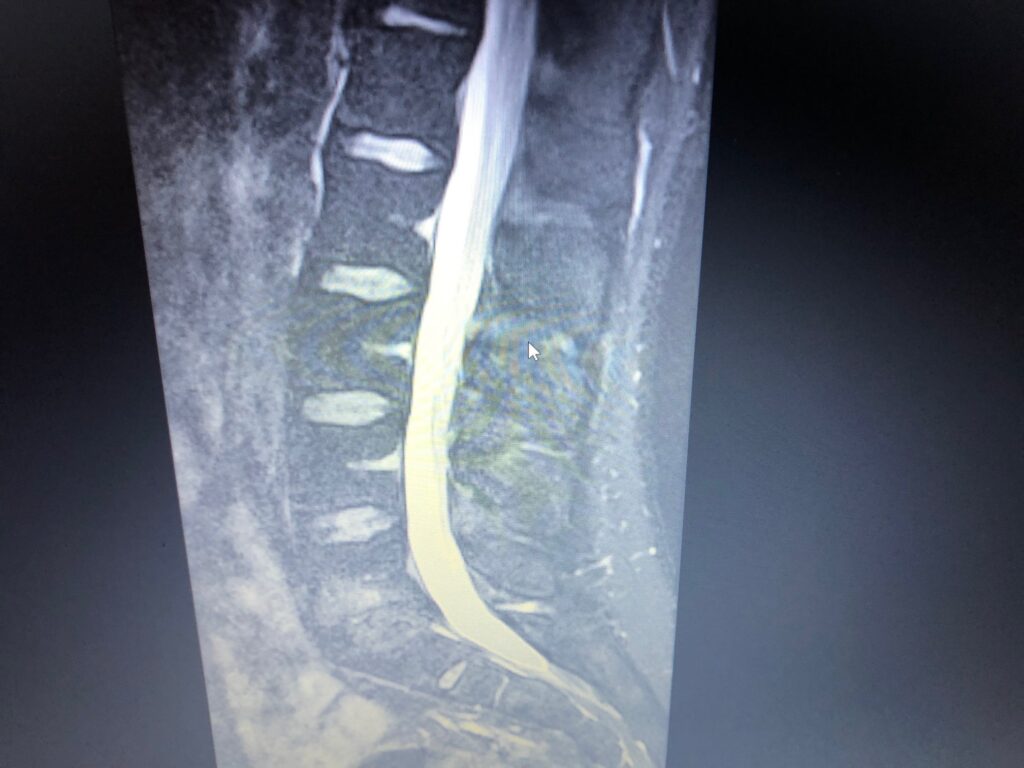

Disc Herniation L5-S1

MRT Study German Sport University Cologne 1998

Univ. Prof. Dr. Ingo Froboese

Quantification of the cartilage structures